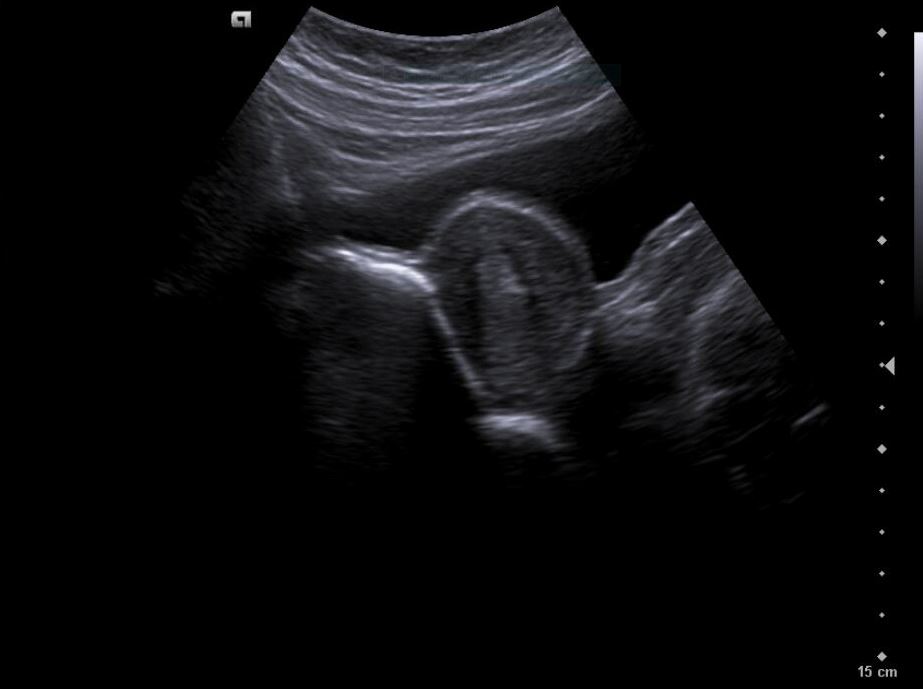

Descripción de los hallazgos ecográficos y las imágenes más relevantes para la resolución del caso

Diagnóstico inicial: Teratoma ovárico derecho versus cuerpo lúteo hemorrágico.

Diagnóstico diferencial: endometriosis, quiste funcional, quiste dermoide.

La paciente es valorada en consulta presencial de ginecología. Ecografía vaginal confirma: